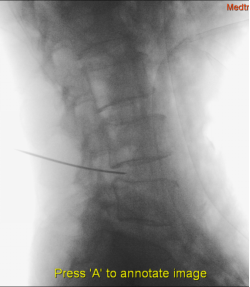

(2)消毒、铺单、麻醉,进行穿刺,理想的针尖的位置在正位像上位于棘突中线(图4),侧位像位于下位椎体后上缘(图5)。

图5 针尖的位置 侧位像位于下位椎体后上缘